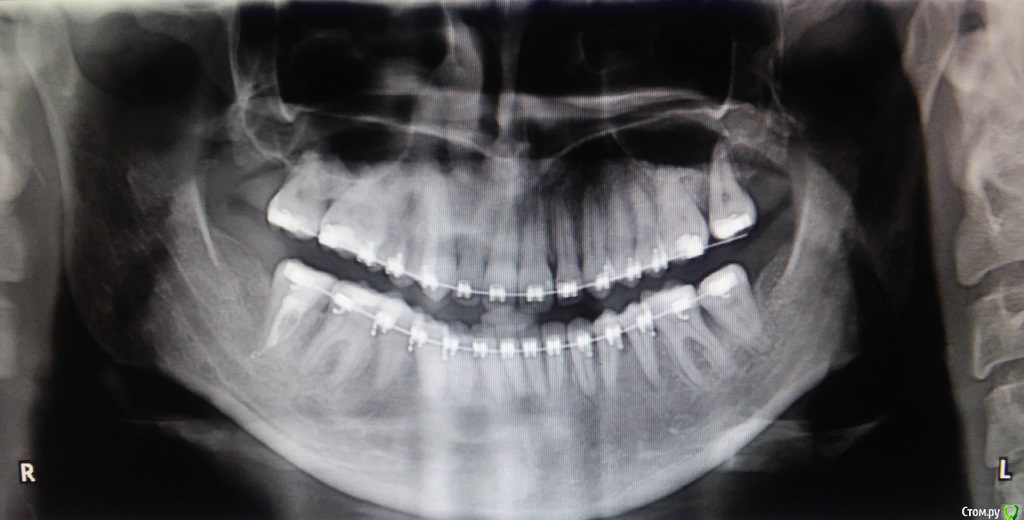

catalystka Опубликовано 14 сентября, 2017 Автор Поделиться Опубликовано 14 сентября, 2017 Готово! ОПТГ, правда, майская, до переклейки брекета. Ссылка на комментарий